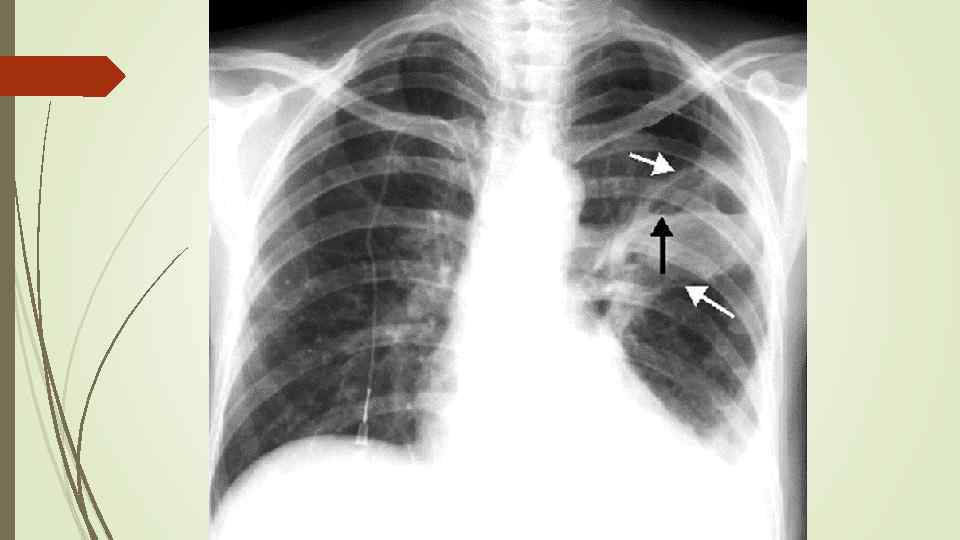

Бронхопневмония Характерно наличие двухсторонних множественных очаговых теней. Контуры очагов нечеткие, интенсивность тени небольшая. Инфильтрация неоднородна. Мелкие, малоинтенсивные очаги не всегда выявляются на снимках. Легочный рисунок усилен на всем протяжении легких. Корни расширены, не структурны. Как правило, отмечается реакция плевры, могут быть и экссудативные плевриты.

Бронхопневмония Характерно наличие двухсторонних множественных очаговых теней. Контуры очагов нечеткие, интенсивность тени небольшая. Инфильтрация неоднородна. Мелкие, малоинтенсивные очаги не всегда выявляются на снимках. Легочный рисунок усилен на всем протяжении легких. Корни расширены, не структурны. Как правило, отмечается реакция плевры, могут быть и экссудативные плевриты.

bronhopneumoni

bronhopneumoni